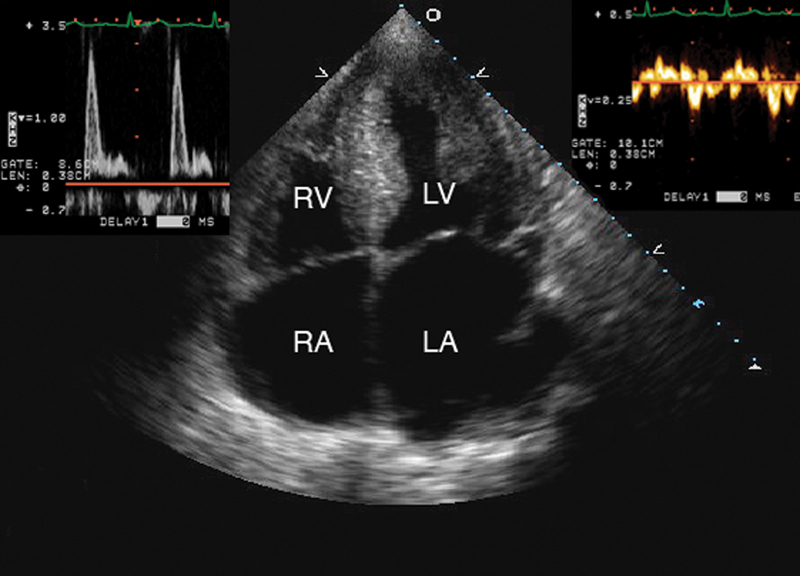

فحوصات تشخيصية لبعض امراض القلب والشرايين التاجية